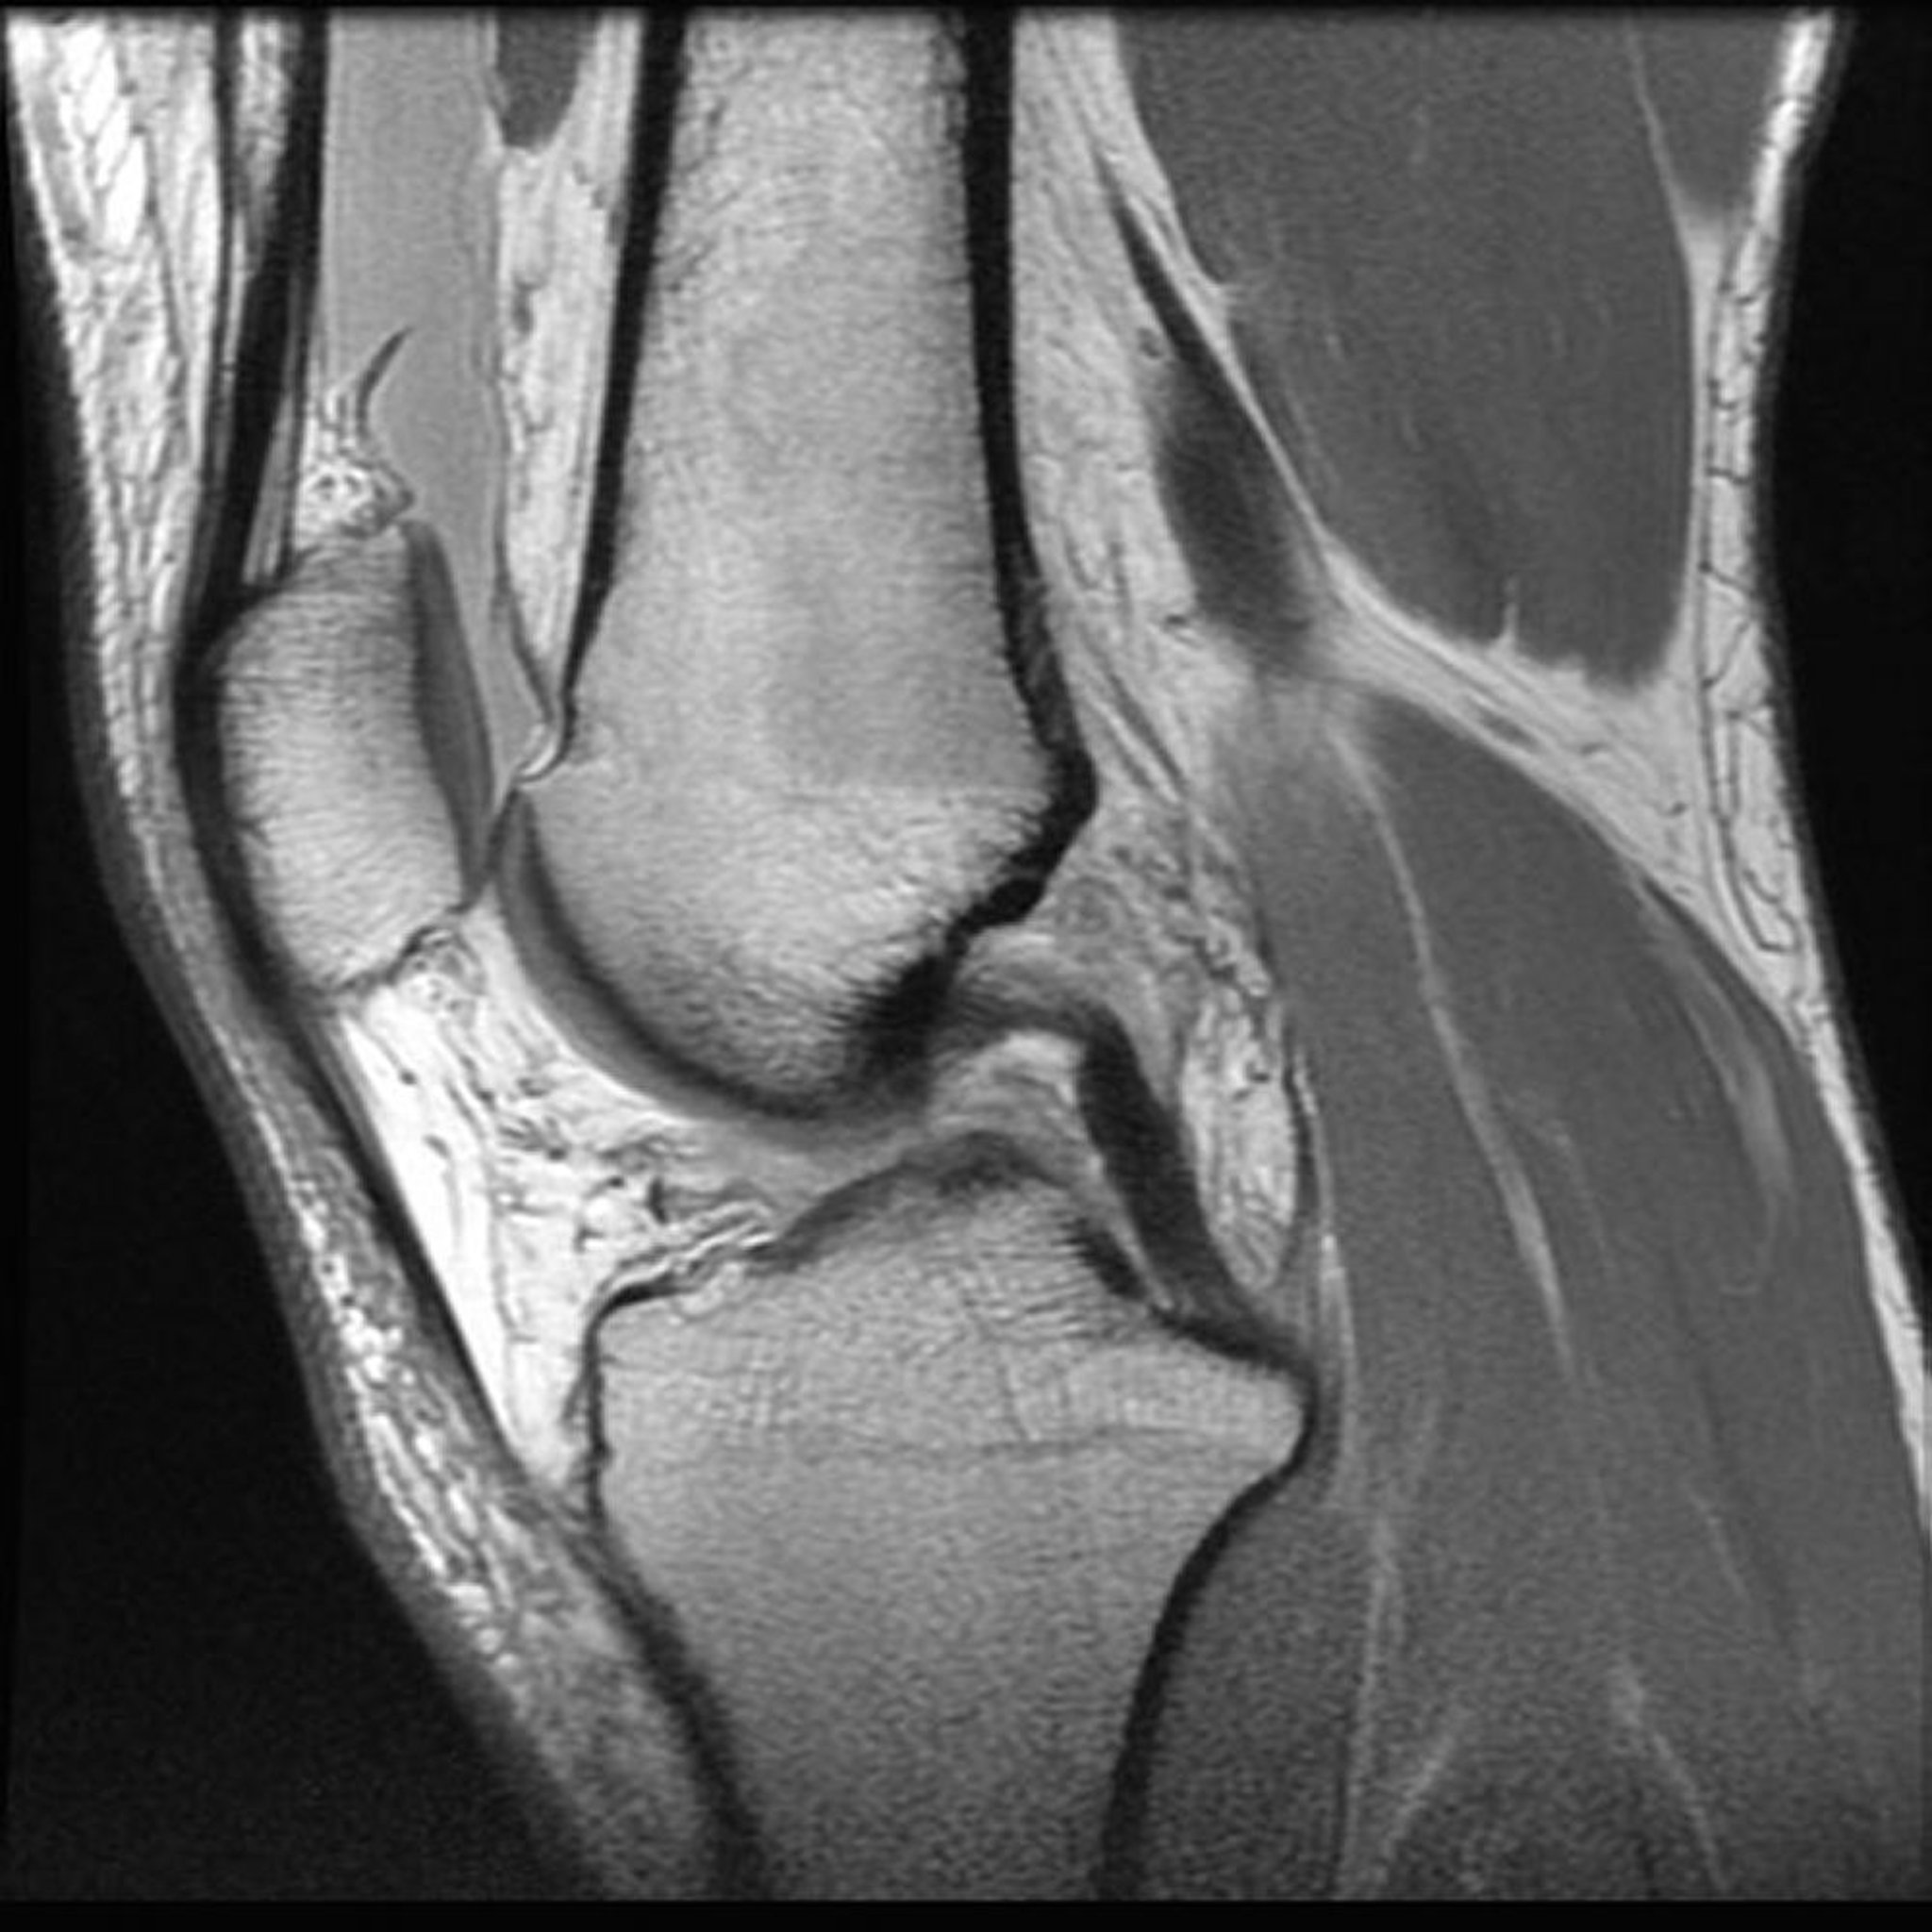

Risonanza magnetica per immagini (RMI) del ginocchio

Immagine fornita dal Dott. Jon A Jacobson.